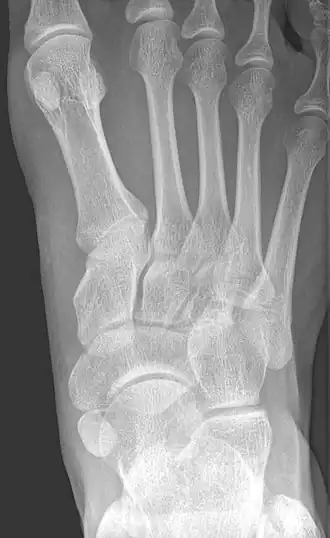

-

From left to right: Type 1, 2 and 3 -